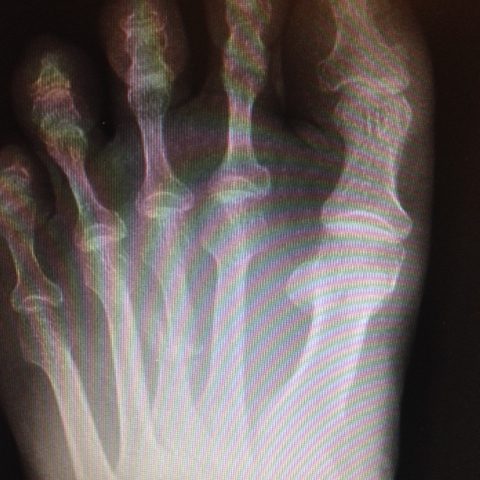

Covering all the common injuries and pain our feet and ankles experience over a lifetime. Click on the links below for more information.